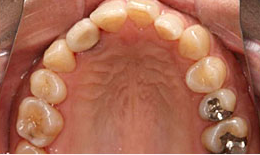

治療後

上顎

保存困難な歯を抜歯後、インプラントを1本埋め込み、セラミックスクラウンを被せた